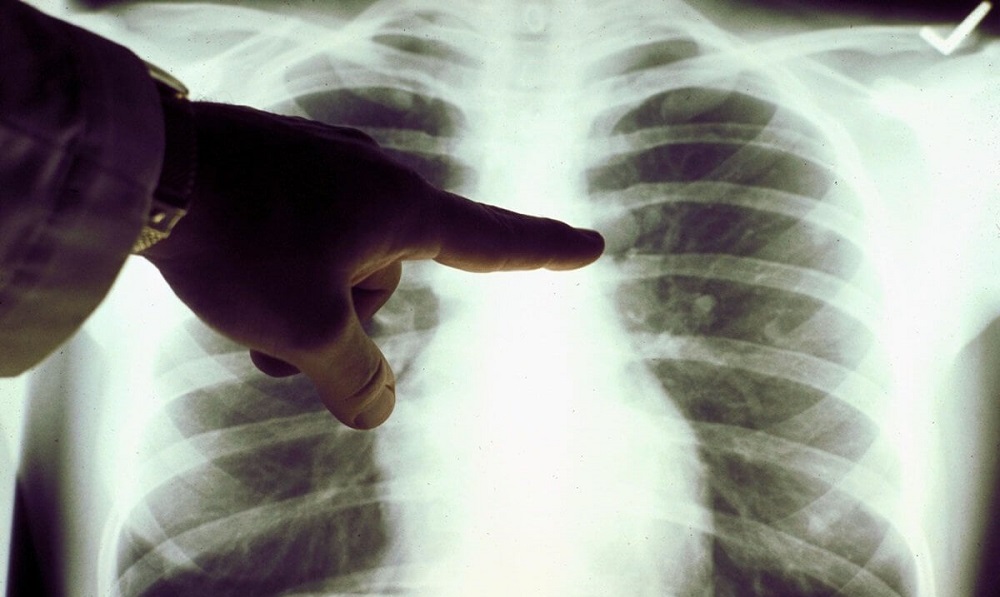

Фото из открытых источников